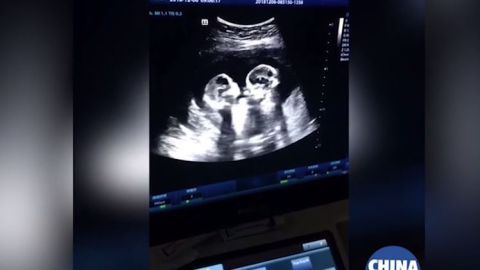

Las gemelas parecieran darse unos cuantos golpes.

En redes sociales se ha viralizado un video de un ultrasonido que se realizó una embaraza en donde se aprecia que está en la dulce espera no solo de uno sino de dos bebés. En próximas semanas, la mujer dará a luz a unas gemelas idénticas.

En el ultrasonido se puede ver el momento exacto en el que estas gemelas pareciera que estuvieran peleando entre ellas, pues hacen movimientos como si se patearan o golpearan mutuamente con sus manos.

Rápidamente, varios medios locales de China, en donde se realizó este ultrasonido, divulgaron las imágenes, las cuales ya le han dado la vuelta al mundo.